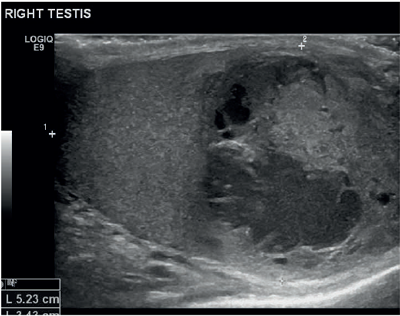

A 26-year-old male presented with a two-week history of testicular pain and swelling. On examination the right testicle was enlarged, indurated and tender. Erythema of the scrotum on that side was also noted. Ultrasound of the testis reported a distorted right testicle with irregular solid and cystic components suggestive of a focal abscess with an inflammatory mass (Figure 1). Doppler study confirmed absence of any obvious internal vascular signal but with an increase in the peripheral vasculature (Figure 2).

Figure 1.